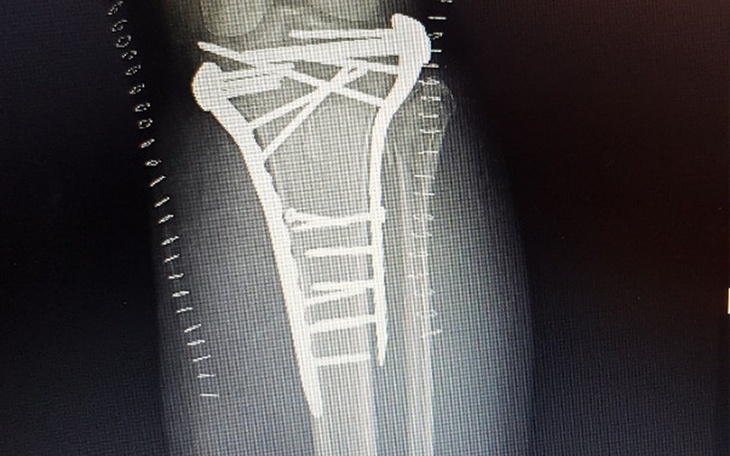

Wpadliśmy na pomysł żeby zorganizować zbiórkę pieniężną dla naszej koleżanki Ani Wojtasik po bardzo ciężkim wypadku w pracy. Zostały uszkodzone kość piszczelowa i strzałkowa na łączeniu z kolanem.